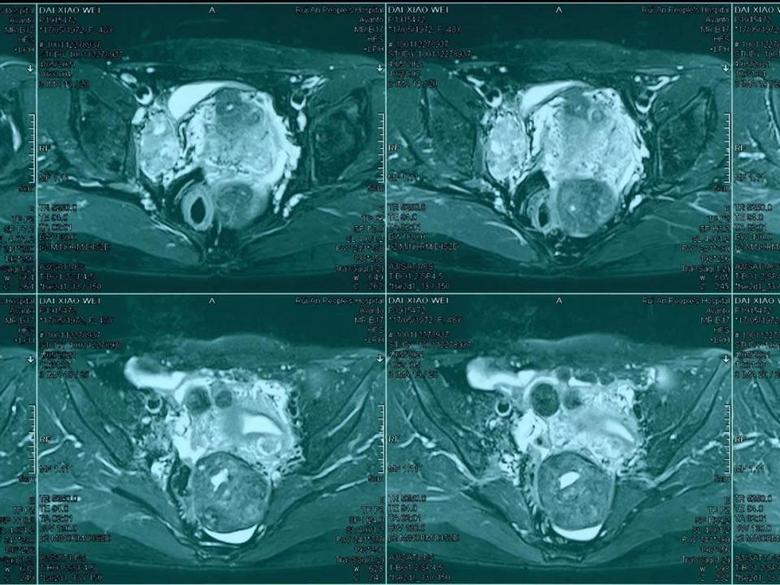

近期,在科室团队努力下,顺利为一腹膜后肿瘤患者腹腔镜微创下切除肿瘤,目前患者康复出院。